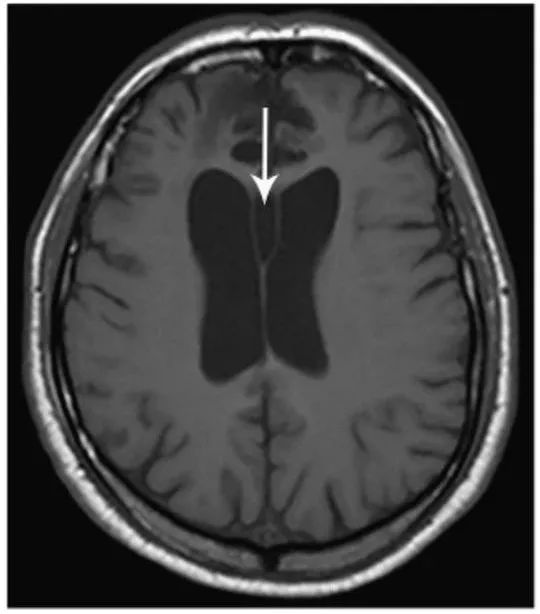

图13 透明隔囊肿

轴位T1WI显示两层透明隔之间正常的空间增大(箭头)。